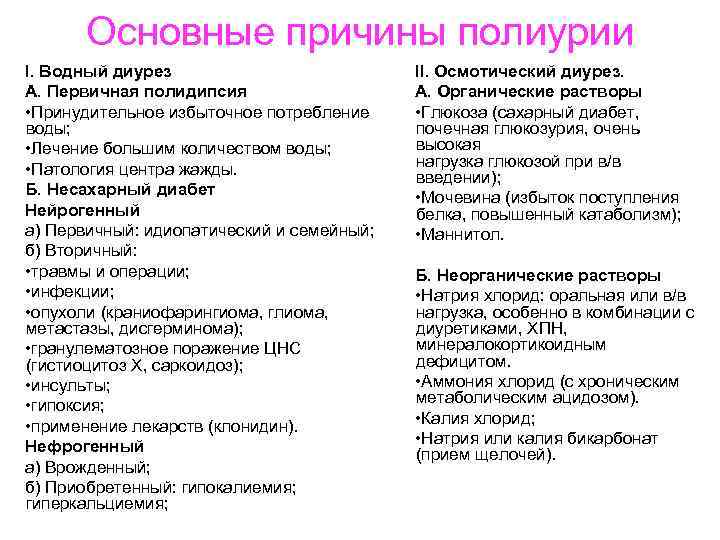

Основные причины полиурии I. Водный диурез А. Первичная полидипсия • Принудительное избыточное потребление воды; • Лечение большим количеством воды; • Патология центра жажды. Б. Несахарный диабет Нейрогенный а) Первичный: идиопатический и семейный; б) Вторичный: • травмы и операции; • инфекции; • опухоли (краниофарингиома, глиома, метастазы, дисгерминома); • гранулематозное поражение ЦНС (гистиоцитоз X, саркоидоз); • инсульты; • гипоксия; • применение лекарств (клонидин). Нефрогенный а) Врожденный; б) Приобретенный: гипокалиемия; гиперкальциемия; II. Осмотический диурез. А. Органические растворы • Глюкоза (сахарный диабет, почечная глюкозурия, очень высокая нагрузка глюкозой при в/в введении); • Мочевина (избыток поступления белка, повышенный катаболизм); • Маннитол. Б. Неорганические растворы • Натрия хлорид: оральная или в/в нагрузка, особенно в комбинации с диуретиками, ХПН, минералокортикоидным дефицитом. • Аммония хлорид (с хроническим метаболическим ацидозом). • Калия хлорид; • Натрия или калия бикарбонат (прием щелочей).

Основные причины полиурии I. Водный диурез А. Первичная полидипсия • Принудительное избыточное потребление воды; • Лечение большим количеством воды; • Патология центра жажды. Б. Несахарный диабет Нейрогенный а) Первичный: идиопатический и семейный; б) Вторичный: • травмы и операции; • инфекции; • опухоли (краниофарингиома, глиома, метастазы, дисгерминома); • гранулематозное поражение ЦНС (гистиоцитоз X, саркоидоз); • инсульты; • гипоксия; • применение лекарств (клонидин). Нефрогенный а) Врожденный; б) Приобретенный: гипокалиемия; гиперкальциемия; II. Осмотический диурез. А. Органические растворы • Глюкоза (сахарный диабет, почечная глюкозурия, очень высокая нагрузка глюкозой при в/в введении); • Мочевина (избыток поступления белка, повышенный катаболизм); • Маннитол. Б. Неорганические растворы • Натрия хлорид: оральная или в/в нагрузка, особенно в комбинации с диуретиками, ХПН, минералокортикоидным дефицитом. • Аммония хлорид (с хроническим метаболическим ацидозом). • Калия хлорид; • Натрия или калия бикарбонат (прием щелочей).